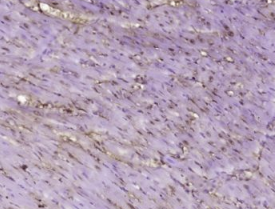

多聚甲醛固定,石蜡包埋(大鼠心脏);经柠檬酸钠缓冲液(pH6.0)煮沸15min后获得抗原;用3%过氧化氢阻断内源性过氧化物酶20分钟;阻断缓冲液(正常山羊血清)37℃30min;用BCSC1多克隆抗体进行抗体孵育IBody,未结合,1:400,4°C下过夜,然后根据SP试剂盒(兔子)说明和DAB染色进行操作。